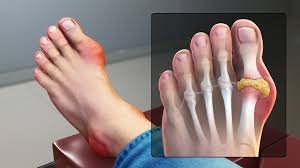

Gout is a metabolic disorder caused by the buildup of uric acid in the blood, leading to the formation of monosodium urate crystals in the joints. This condition results in severe pain, swelling, and inflammation, especially in the big toe joint, known as Podagra. Gout is more common in men after age 20 and in women after menopause. Uric acid levels above 7.0 mg/dL in men and 6.0 mg/dL in women increase the risk. Normally, uric acid is excreted by the kidneys, but overproduction or poor elimination causes crystal deposits. It has historically affected notable figures and is linked to lifestyle, diet, and genetics.